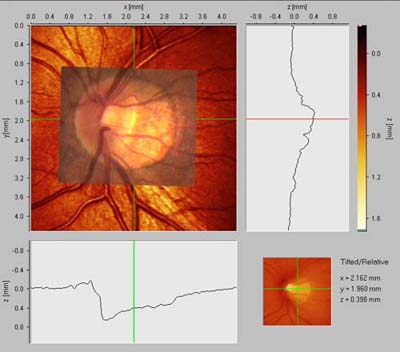

Peripapilární atrofie

Před 100 lety Elschnig a Bucklers rozpoznali souvislost mezi peripapilární atrofií a glaukomem a cirkulární peripapilární atrofii v pozdních stadiích glaukomové neuropathie nazvali "halo glaucomatosus". Oftalmoskopicky jsou patrné dvě zóny: beta je centrální, alfa periferní.

Zóna ALFA:

nepravidelná hypo a hyperepigmentace a ztenčení chorioretinální tkáně. Je projevem nepravidelností pigmentu retinálního pigmentového epitelu. Způsobuje relativní skotom.

Zóna BETA:

je světlejší zóna s viditelnou sklérou a velkými cévami cévnatky.

Nepřímá úměra jejího rozsahu k výši nitroočního tlaku: Čím vyšší tenze, tím menší atrofie. Čím nižší tenze, tím větší atrofie.